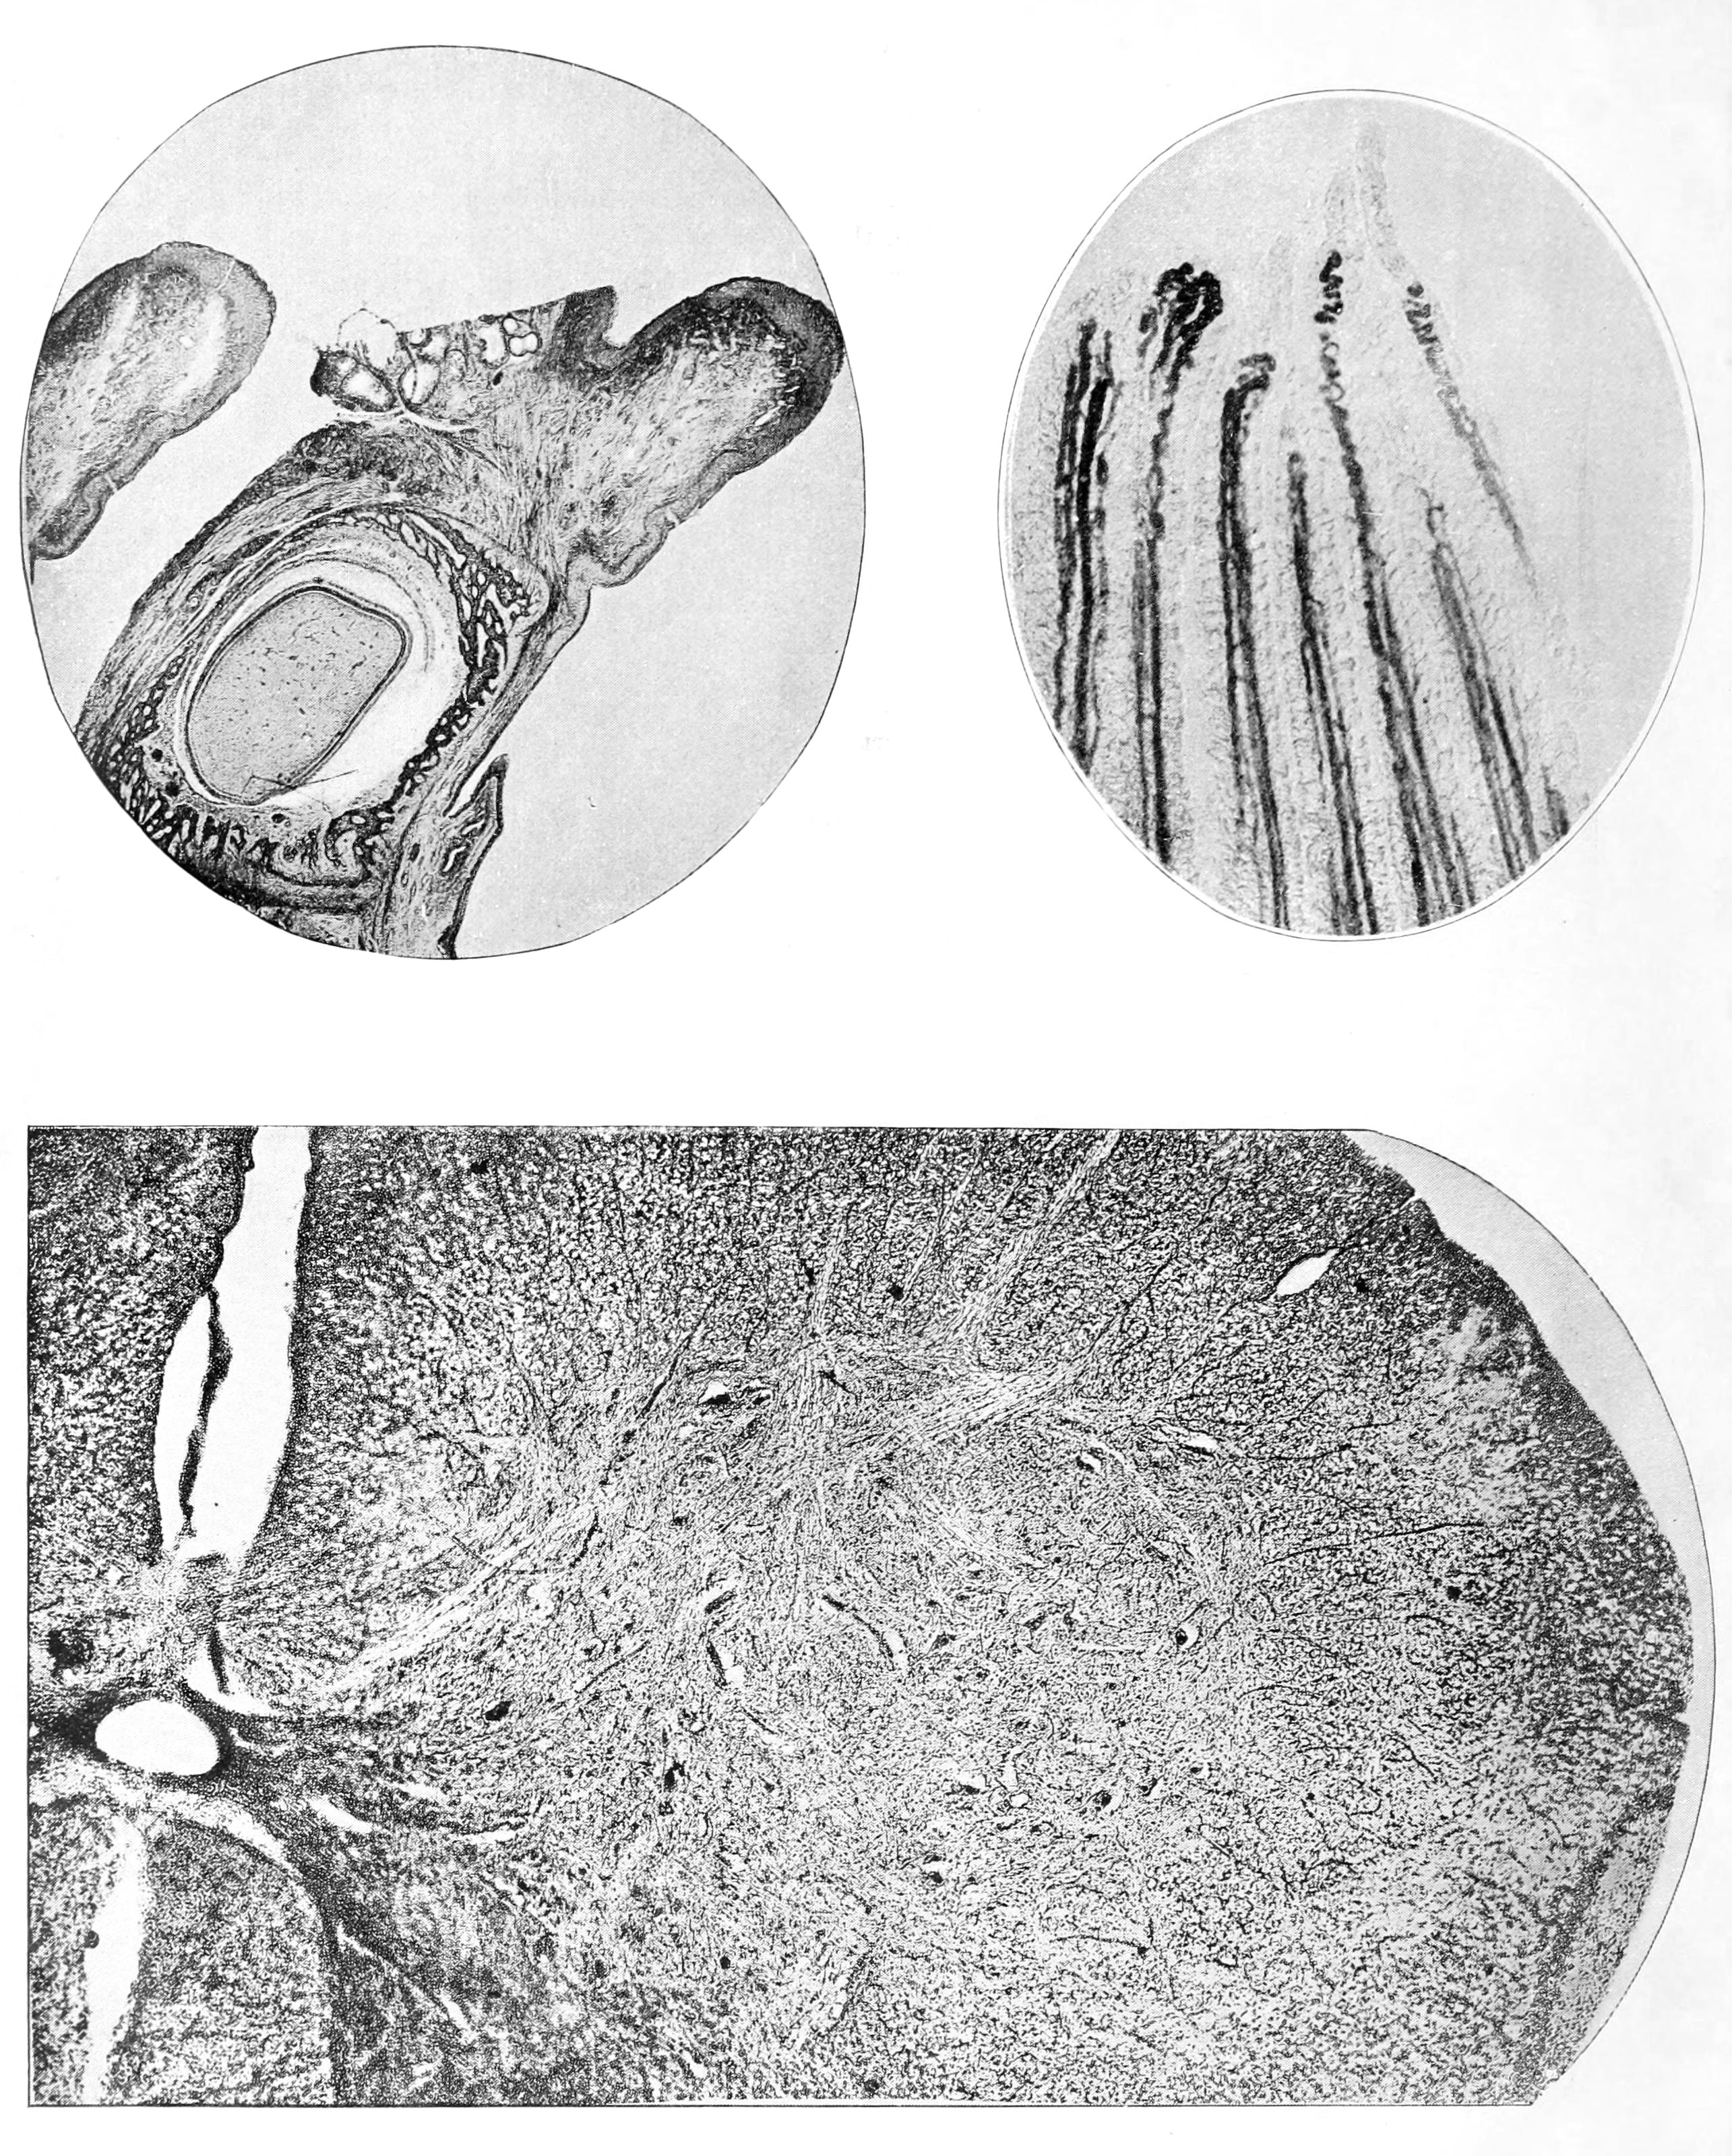

金韵梅论文中的显微摄影照片,上半部分是猫牙齿横切,下半部分是猫脊髓横切:

金韵梅发表的论文《The Photo-Micrography Of Histological Subjects》其中地理信息是中国,厦门:

Y. May King. The Photo-Micrography Of Histological Subjects. New York Medical Journal, July 2, 1887:7-11.